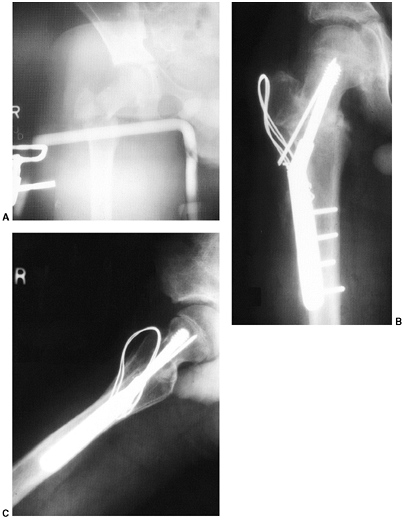

![]() |

|

Figure 33.17 Type II supracondylar humerus fracture with medial impaction and varus alignment. A, B:

Anteroposterior and lateral views of a type II supracondylar humerus fracture with medial impaction. Note that although there is little displacement on the lateral view, the Baumann angle is 0 degrees on the anteroposterior. C, D: Anteroposterior and lateral intraoperative views of the distal humerus after the impacted fracture was reduced and fixed with divergent lateral pins. Note that on the anteroposterior, the Baumann angle is restored, and on the lateral, the anterior humeral line intersects the capitellum. The reduction was maintained during the postoperative period. |